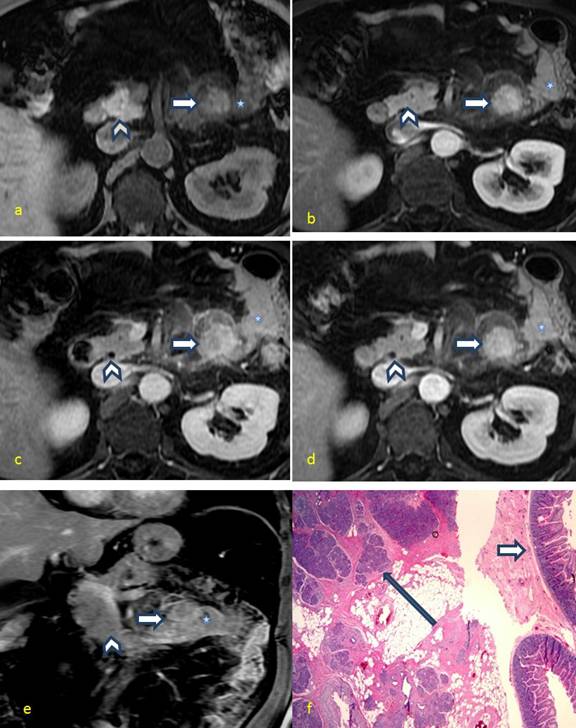

With the given atypical findings, it was decided to perform MRI study with MRCP sequences. On the next day after CT, the MR examination was done on a 1.5T system (MR Signa EXCITE, GE Healthcare). MRCP sequence radial SSFE, coronal 2DSSFE with fat-sat and 3D FSE; then, axialT2-weighted FSE (7/8 mm; 80 and 160 TEs), axial and coronal FIESTA (5mm/0gap), axial eDWI (7mm/0gap), axial LAVA Flex in-phase and out-phase (5mm/0gap) and dynamic contrast-enhanced axial LAVA Flexin early arterial (triggered at right atrium), 30 sec, 1 min and 3 min(5mm/0gap) followed by coronal in 5 minutes after intravenous contrast injection (18 cc of Multihance; gadobenate dimeglumine 0.1 mmol/kg) were performed. All these sequences were done during breath-hold except axial T2-weighted and 3D FSE MRCP which were performed with respiratory trigger. These images revealed a 2.5 x 2.8 cm focal mass at the duodenojejunal flexure which mimicked the signal intensity of the adjacent normal pancreatic parenchyma in all sequences, suggesting ectopic pancreatic tissue (Figure 2a-e). The presence of surrounding fat stranding, normal adjacent pancreas, and a clinical diagnosis of acute pancreatitis raised the possibility of acute ectopic pancreatitis. Immediate surgery was potentially avoided and treated with conservative management for acute pancreatitis until symptoms subsided.

Figure 2. Dynamic contrast-enhanced MR images performed before IV contrast, early arterial, 30 sec, 1 minute and 3 minutes after IV contrast administration. (a-d) A jejunal mass (block arrow) near the duodenojejunal flexure shows enhancement nearly similar to the normal native pancreas (arrow head).(e) MRI coronal image 3 minutes after contrast injection demonstrates the relationship of ectopic pancreatic tissue to jejunum and native pancreas. (f) Low power view of the jejunal mass biopsy shows dark purple stained pancreatic acini (long arrow) and ducts within the submucosal layer of jejunum and also shows intestinal villi with glands (short arrow) on the pink stained muscularis mucosa. These findings confirm the ectopic location of the pancreatic tissue within the jejunal wall. Jejunum is marked as¶. |